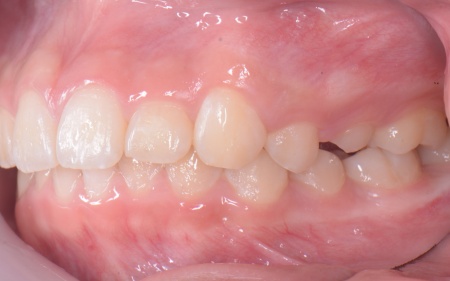

10歳女の子 成長期を利用した小児矯正治療で八重歯を改善した症例

拝見したところ、上の犬歯が歯列の外側に飛び出すように生えている、いわゆる八重歯でした。

さらに、上下の歯全体がデコボコに生えている「叢生(そうせい)」と呼ばれる状態で、これは歯が正しい位置に並ぶためのスペースが不足していることが原因だと考えられます。

また、治療にあたりお口全体のバランスを確認したところ口元の突出はなく、顎のサイズはやや小さめですが、成長期であることから歯列の拡大が可能な状態だと判断しています。

最後に、歯並びが整って見た目や噛み合わせにも問題がないことを確認し、装置を取り外して第1期矯正治療を終了しました。

現在も経過観察を継続していますが、歯が元の位置に戻る後戻りも見られず、残っている乳歯から永久歯への生え変わりも順調に進んでいます。